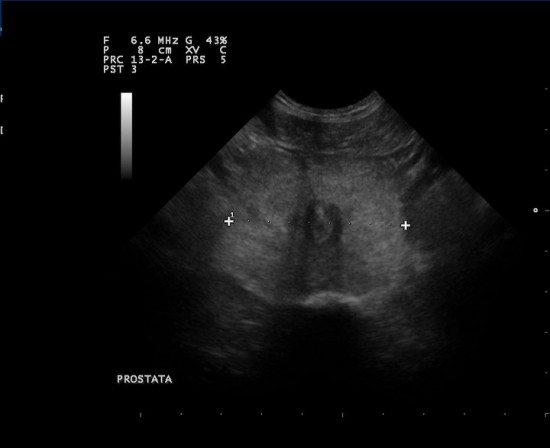

Le più comuni patologie prostatiche del cane includono l’ipertrofia prostatica benigna (benign prostatic hypertrophy o BPH), la metaplasia squamosa, le cisti prostatiche, le cisti paraprostatiche, le prostatiti e le neoplasie prostatiche. La BPH è una condizione spontanea e correlata all’età dei cani maschi interi, che occorre in più dell’ 80% dei cani sopra i cinque anni di età e che è spesso associata a segni clinici quali costipazione, variazioni di forma e consistenza delle feci, presenza di sangue nelle urine, incontinenza urinaria o alterazioni nella frequenza della minzione e del colore delle urine, difficoltà nell’urinare. La BPH risponde alla castrazione o al trattamento farmacologico. La BPH spesso determina comparsa di infezioni, formazione di ascessi prostatici, prostatiti, cisti e neoplasie. Non fare che una semplice BPH si possa trasformare in qualcosa di più serio: basta effettuare un controllo prostatico annuale (visita clinica ed ecografia) dopo i cinque anni di età, senza dover aspettare la comparsa di sintomi apprezzabili all’occhio del proprietario.

Le più comuni patologie prostatiche del cane includono l’ipertrofia prostatica benigna (benign prostatic hypertrophy o BPH), la metaplasia squamosa, le cisti prostatiche, le cisti paraprostatiche, le prostatiti e le neoplasie prostatiche. La BPH è una condizione spontanea e correlata all’età dei cani maschi interi, che occorre in più dell’ 80% dei cani sopra i cinque anni di età e che è spesso associata a segni clinici quali costipazione, variazioni di forma e consistenza delle feci, presenza di sangue nelle urine, incontinenza urinaria o alterazioni nella frequenza della minzione e del colore delle urine, difficoltà nell’urinare. La BPH risponde alla castrazione o al trattamento farmacologico. La BPH spesso determina comparsa di infezioni, formazione di ascessi prostatici, prostatiti, cisti e neoplasie. Non fare che una semplice BPH si possa trasformare in qualcosa di più serio: basta effettuare un controllo prostatico annuale (visita clinica ed ecografia) dopo i cinque anni di età, senza dover aspettare la comparsa di sintomi apprezzabili all’occhio del proprietario.